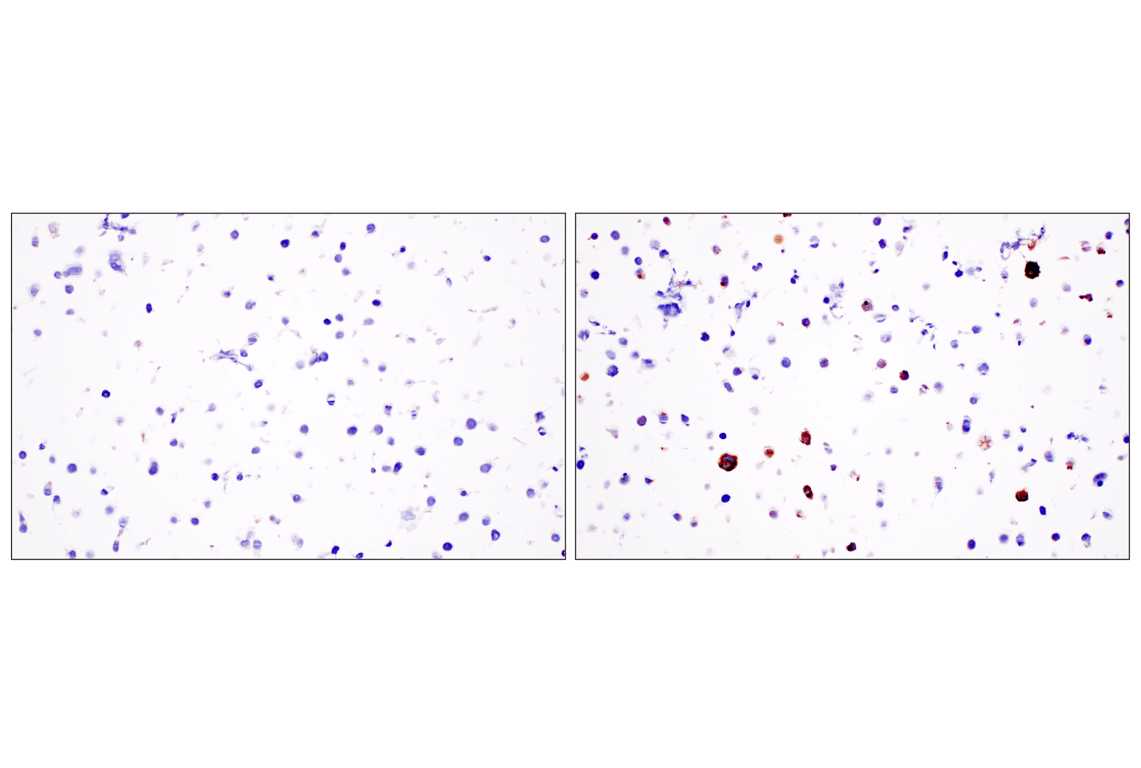

Immunohistochemical analysis of paraffin-embedded 293T cell pellet, untransfected (left) or CXCL13-transfected (right), using CXCL13 (F6A4R) Rabbit mAb.

Immunohistochemistry Image 7: CXCL13 (F6A4R) Rabbit Monoclonal Antibody